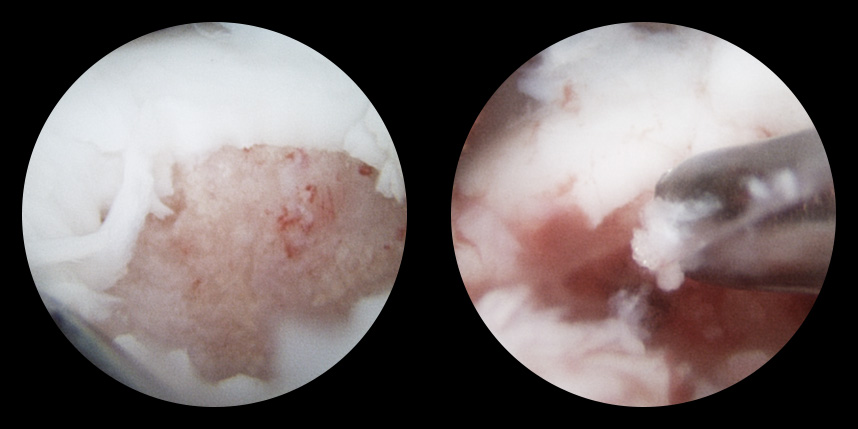

손상된 연골 부위에 작은 구멍을 뚫어 골수에서 나오는 줄기세포를 이용하여 연골 재생을 유도하는 방법으로 근본적으로 섬유연골(정상연골보다는 약한 연골)로 재생된다고 알려져 있습니다.

특수하게 농축하여 제작된 6% 콜라겐(리젠실603) 또는 9% 콜라겐(이엔카티)을 천공술을 시행한 부위에 덮어 주어 미세천공술 단독보다 좋은 치료 결과를 기대할 수 있습니다.

본원에서는 미세천공술, 콜라겐주입술, 카티스템 치료를 주로 하고 있습니다.

타병원 미세천공술 실패 후 통증으로 내원하신 사례

* 환자에게 받은 소중한 자료입니다.